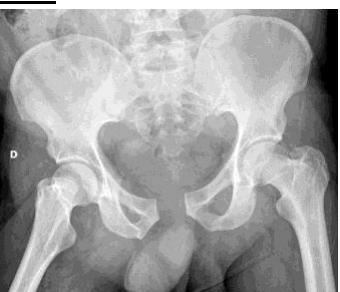

A teenager with acute onset of pain in the right hip during a run. He sustained the injury seen in the x-rays with a white arrow. This injury usually occurs due to a forceful eccentric contraction of which of the following muscles?

- C. Rectus femoris

- Sartorius

Pelvic Anatomy

Which of the following muscles is attached to the structure pointed by the arrow?

- C. Sartorius

Note: Arrow was pointing at ASIS (Anterior Superior Iliac Spine)